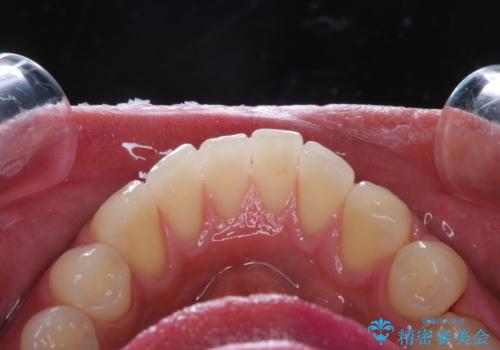

親知らずを抜いて1週間後にPMTC 歯のクリーニング

- 親知らずの抜歯後の約1週間後に抜糸(縫った部分の糸とり)で来院されました。その際、抜歯後は傷口が怖くて歯磨きが上手くできず、汚れや口臭が気になるためクリーニングも希望されました。

抜歯後は多少出血したり、違和感や痛みを感じたりすることがあります。そのため親知らずを抜いたり、外科的な処置をするといつも通りの歯磨きがしづらくなります。また、傷口の周りが心配で、歯ブラシをするのが怖くなるものです。抜歯後落ち着いたら、歯科医院にて専門の機械を使用しクリーニングをすることがおすすめです。抜歯前や後にPMTCを行うことで、お口の中の健康維持につながり、その後の感染・腫れ・口臭予防などになります。

親知らず抜歯後正常に治癒が進んでいれば1週間後から可能です。